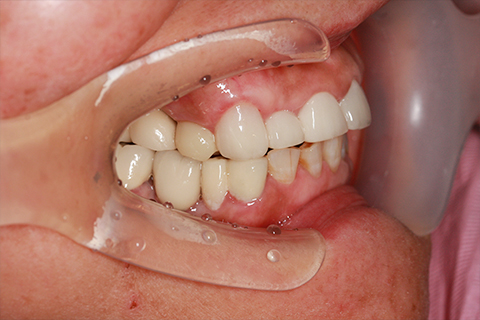

症例4

- 年齢・性別

- 60歳

- 治療期間

- 6ヶ月

- 抜歯

- 残根抜歯のみ

- 治療費

- 198万円

- 備考

- 右上5.6 右下5 左下4.5.6欠損

- 治療内容

- 6本のインプラントを右左側に2回に分けて埋入

- 施術の副作用(リスク)

- オペによる知覚障害。インプラントによる歯肉炎。インプラント脱落。